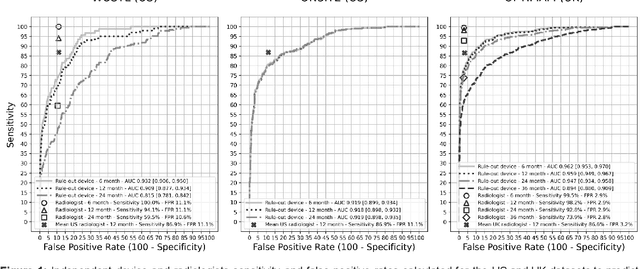

A deep learning algorithm for reducing false positives in screening mammography

Apr 13, 2022

Screening mammography improves breast cancer outcomes by enabling early detection and treatment. However, false positive callbacks for additional imaging from screening exams cause unnecessary procedures, patient anxiety, and financial burden. This work demonstrates an AI algorithm that reduces false positives by identifying mammograms not suspicious for breast cancer. We trained the algorithm to determine the absence of cancer using 123,248 2D digital mammograms (6,161 cancers) and performed a retrospective study on 14,831 screening exams (1,026 cancers) from 15 US and 3 UK sites. Retrospective evaluation of the algorithm on the largest of the US sites (11,592 mammograms, 101 cancers) a) left the cancer detection rate unaffected (p=0.02, non-inferiority margin 0.25 cancers per 1000 exams), b) reduced callbacks for diagnostic exams by 31.1% compared to standard clinical readings, c) reduced benign needle biopsies by 7.4%, and d) reduced screening exams requiring radiologist interpretation by 41.6% in the simulated clinical workflow. This work lays the foundation for semi-autonomous breast cancer screening systems that could benefit patients and healthcare systems by reducing false positives, unnecessary procedures, patient anxiety, and expenses.